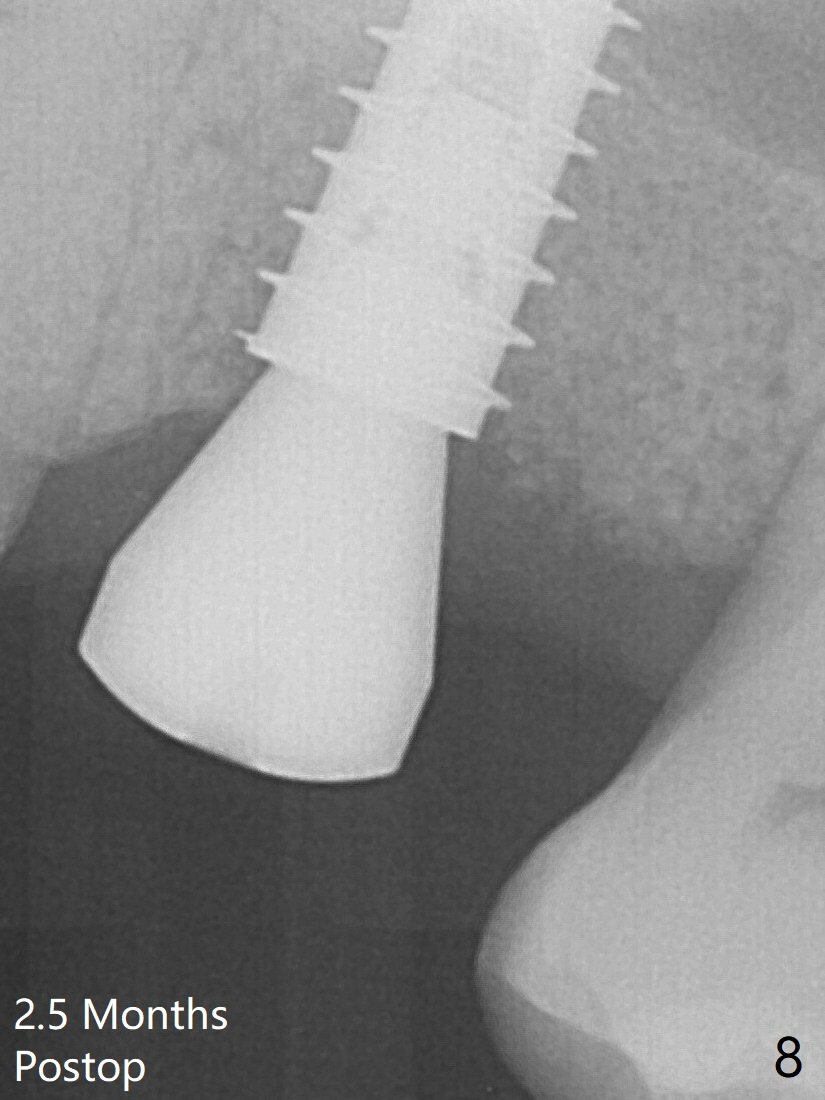

A 5x9 mm implant is placed slightly mesial; after placement of a 6.5x4(2) mm abutment and insertion of collagen plug in the palatal socket (radiolucent area distal to the implant), Vera graft is placed in the remaining socket space (Fig.5 *).  Nasal hemorrhage persists 1.5 months postop (Fig.6).   The distal gingiva is slightly tender and erythematous; a 6x4 mm healing abutment is placed 2.5 months postop (Fig.8).